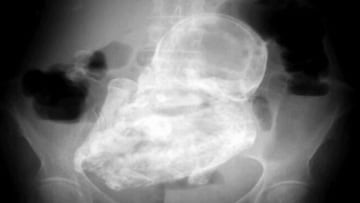

Hay casos en el mundo de la ciencia y la medicina que sorprenden incluso a los profesionales. El del “bebé de piedra” es uno de esos que se quedan grabados en la piel. Una mujer de Marruecos pasó 46 años de su vida con el feto de su hijo dentro de su cuerpo. Este fenómeno se conoce como “embarazo ectópico” y solo hay 300 casos registrados en el histórico de la medicina moderna.

La pregunta del millón: ¿cómo sobrevivió con el feto dentro? Este raro caso ocurre en 1 de cada 10.000 embarazos, cuando el feto crece alrededor del abdomen de la madre. Con el seguimiento adecuado se ataja desde una etapa muy temprana del embarazo. Cuando ocurre en una fase donde el bebé está muy desarrollado, separarlo de los órganos clave es una tarea casi imposible de realizar sin que mueran tanto el bebé como la madre.

En ese punto el feto no recibe el suficiente corriente de sangre que pueda “expulsarlo” por su propia corriente, así que el cuerpo lo que hace es tirar del mismo proceso inmunológico que cuando encuentra un objeto donde no debe: se calcifica.